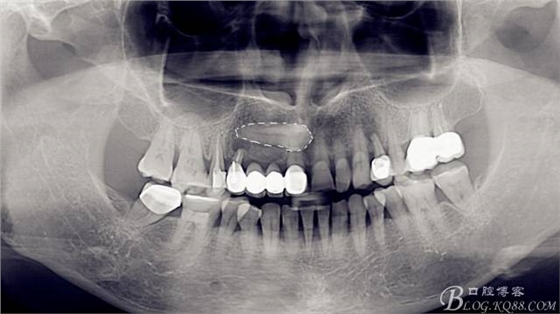

全景片,此時此刻已經(jīng)拔除了A4,搔刮牙槽窩去除了囊腫。

CBCT檢查:A1和A4根尖區(qū)有一水平橫置多生牙,多生牙會影響A1到A4區(qū)域的種植手術(shù),建議外科手術(shù)拔除多生牙。